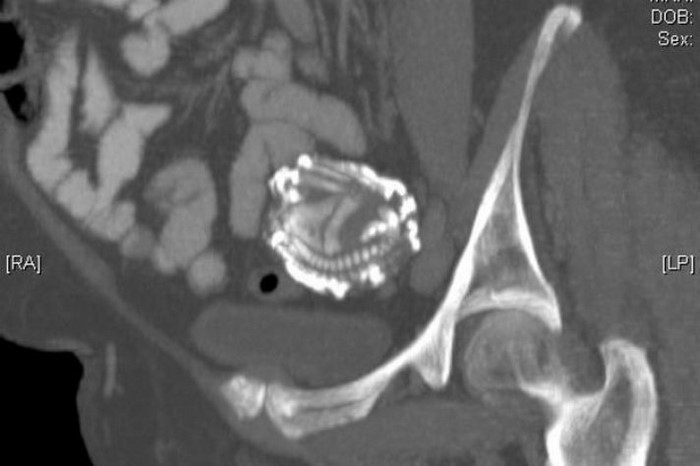

Sólo una imagen obtenida con resonancia magnética podría arrojar luz sobre el cuadro completo. Como resultó, el «tumor» era no era otra cosa que un niño petrificado, aquel que nunca llegó a nacer 46 años atrás.

El feto se desarrolló en la cavidad abdominal, debido a un embarazo ectópico, y por poco no hizo estallar una trompa de Falopio. Luego, cuando murió, el sistema inmunológico de la madre lo «reconoció» como un cuerpo extraño, y formó un «capullo» protector de calcio alrededor suyo.

Vale la pena señalar que el caso de Aboutalib, aunque fuera de lo común, no es el único caso. Este raro fenómeno es conocido por la medicina como litopedion, nombre que recibe un feto muerto, que luego fue calcificado. Tales casos son muy raros: en los últimos 400 años se registraron menos de trescientos.

En este misterioso «capullo de calcio», la criatura muerta puede permanecer durante décadas, y gracias a él, el cuerpo de la madre puede protegerse de la infección.

Por ejemplo, el embrión de la imagen de arriba estuvo en el útero de su madre durante 55 años. ¡Lo más interesante es que durante este período la mujer sobrevivió cinco embarazos más, sin problemas ni complejidades!